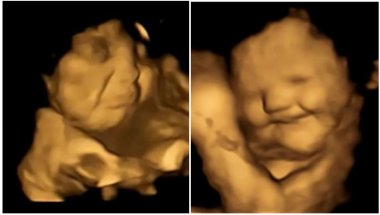

Foto: FETAP Study/Fetal and Neonatal Research Lab/Durham University

Istraživači su primetili da fetusi takođe prave plačni izgled lica kada osete ovo zeleno povrće. Dok su prethodna istraživanja pokazala da se naši ukus možda razvija i pre rođenja i da na njega može da utiče majčina ishrana, nova studija pokušala je da zaviri i direktno posmatra reakcije nerođenih beba na različite ukuse.

Tim naučnika je nakon pregleda obavljao analizu svakog snimljenog kadra i posmatrao izraze lica fetusa, uključujući i kombinacije grimasa koje su izgledale kao plač ili smejanje. Napravljeno je više od 180 ultrazvučnih snimaka na 99 fetusa, koji su skenirani u 32. i 36. nedelji trudnoće.

Plačni izrazi lica bili su dva puta češći kada su majke konzumirale kapsule sa keljom u poređenju sa fetusima čije su majke uzimale kapsule sa šargarepom ili nisu uopšte uzimale kapsule. U slučaju kapsula sa ukusom šargarepe, lica nerođenih beba su često dobijala izraz osmehivanja.